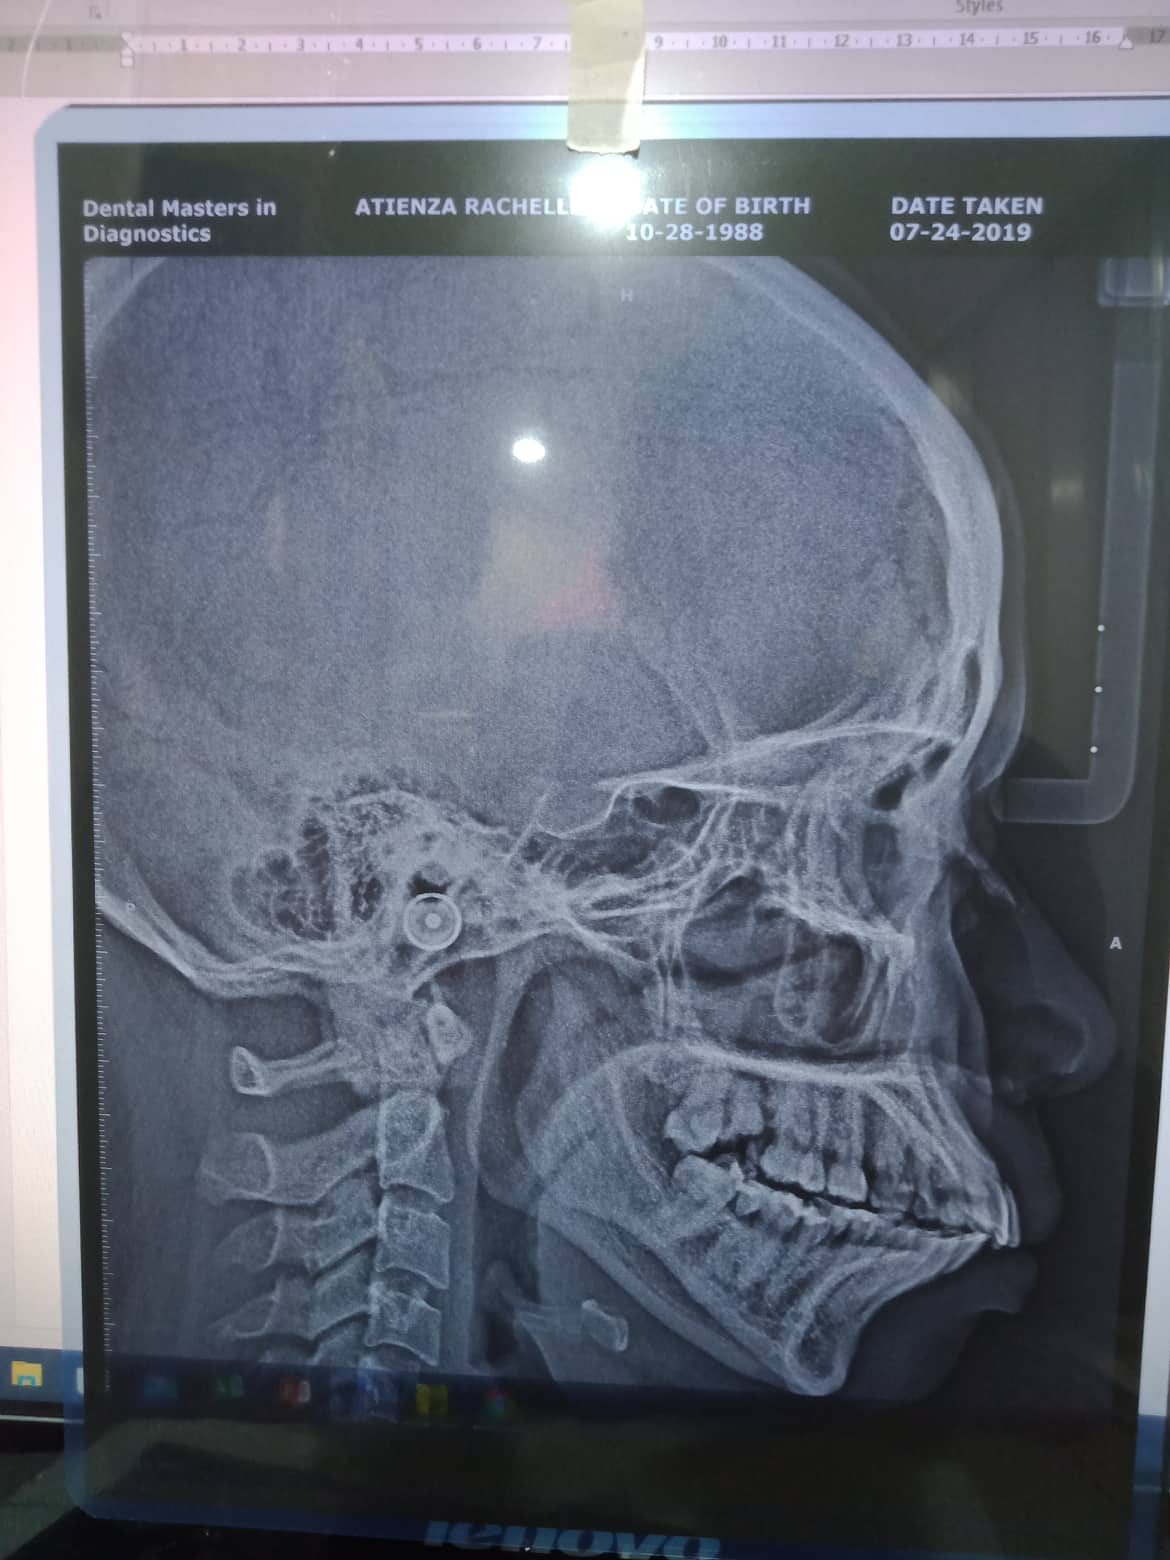

- Last Name

- Atienza

- First Name

- Rachelle

- Middle Name

- Baldomero

- Birthdate

- October 28, 1988

- Age

- 30

- Procedure

- 07/24/21- IPR23 U to left 09/23/21 16*16ss upper/ 16*16 lower all upper to left LC 11/12 mesial 10/16/21 upper to left S-elastic 16 to 46 fox lower tipping of incisal anterior double chain 11/27/21- adj same wire class 2 elastic force 2 chain upper/ rw 42 02/05/22- same wire 03/20/22- chain upper 16x 16 ss UL/ ind lower/ fox 24-25 to 34-35 04/23/22 - chain upper 4/23/22- same wire/ distalized 16 for implant placement/ 13 to 46 rabbit 06/18/22- adj same wire. class 2 elastic rabbit 08/26/22 - irrigate w/ aquolab; same wire; chain upper; change rw 42 9/19/22 - implant #14 CGF & PRF ( Bio- Oss 0.25-1mm ) implant size -4.0x11.5mm 10/21/22 - UL SAME WIRE/ RPI b/w #43-44, U CHAIN/ REATTACH #36 11/18/22-dpforImplant/adj 1/27/23-ADJ 05/13/23- installation of abutment/Impression taking 06/21/25 OP w/ Air polisher retainer U/L